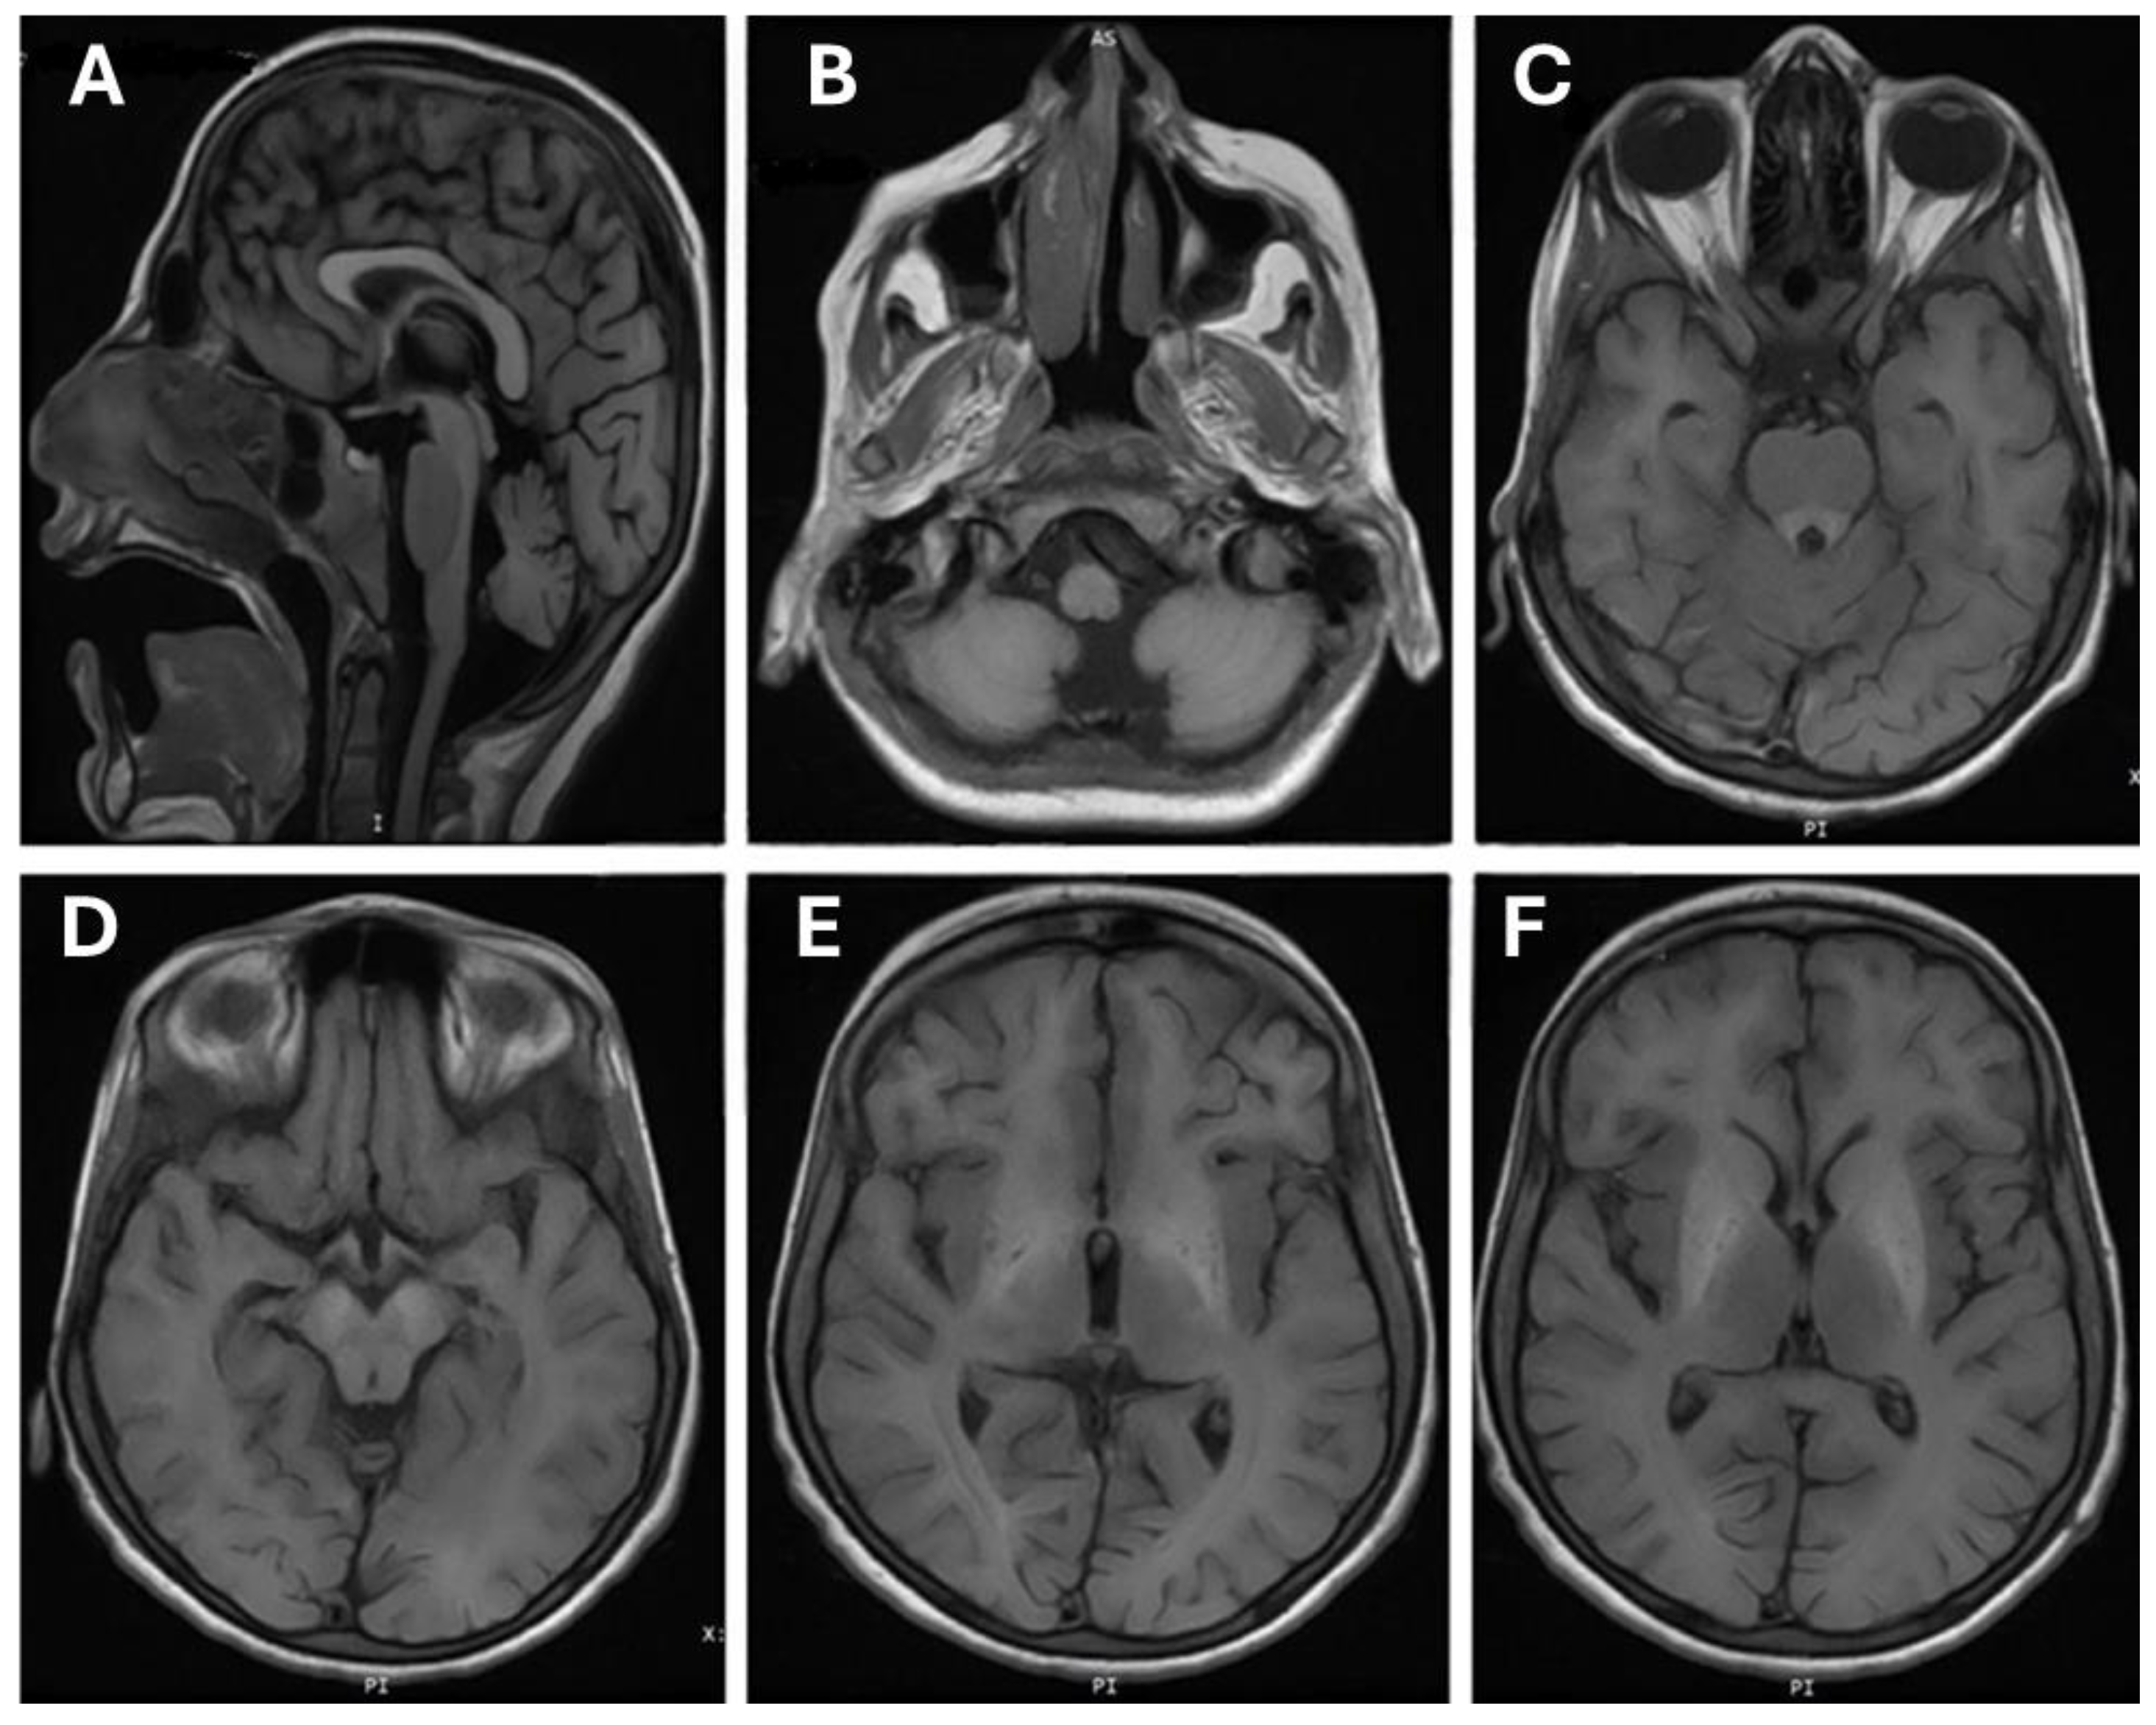

A brain MRI performed on individual (III-3) at the age of 11 years suggests evidence of bilateral symmetrical signal alteration involving the basal ganglia, particularly the globus pallidi and substantia nigra, with suspicious involvement of the dorsal brainstem and dentate nuclei (Figure 2). These alterations appear as high signal intensity on T1-weighted images (T1-WI), with no observed signal alteration on T2-WI. A blooming effect is seen only in the globus pallidi, indicating the iron/or manganese deposition. However, no diffusion restriction is noted.

Figure 2.

Brain magnetic resonance imaging (MRI) of patient (III-3). (A) Cerebellar atrophy flair saggital sequence flair; (B) hypoplasia of vermis axial T1; (C) increased signal from the basal ganglia down to the brain stem mainly midbrain (cerebri) and pones (ventral). Ventrical pons around 4th ventricle; (D) midbrain (cerebri bilateral); (E) frontal bilateral white matter hypersignal; (F) continuation of hypersignal to basal ganglia signs of hypomyelination.

The differentiation between grey and white matter is preserved. Moreover, there are no signs of acute intracranial infarction or hemorrhage. Furthermore, the ventricular system and subarachnoid spaces appear normal, without midline shift, hydrocephalus, brain edema, or herniation. The cerebellum shows diffuse mild atrophy. The imaged vessels are patent, and the orbits and mastoid air cells show no abnormalities. Chronic inflammatory changes are observed in the sinuses.